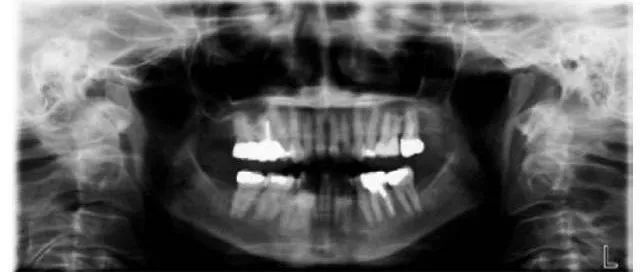

√种植前牙槽骨的质、量的评价及种植体大小、长短的确定。

√牙列缺失复杂修复前基牙的评估。

√根管充填、镶牙、种植、矫正效果的复查、评估。